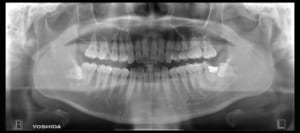

まず、このようなレントゲンを撮影したことはほとんどの方があると思いますが、

通称「パノラマ、パントモ」と言います。

口腔内を俯瞰的に確認するにはこれが最も優れたレントゲン写真になります。

実際これらをよく観察すると、

赤丸のところが虫歯になっています。

私たち歯科医師はこのパノラマでも

ある程度虫歯がある部分は確認できるのですが、やはり見落としもどうしても出てきてしまいます。